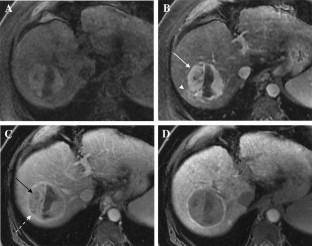

The Liver Imaging Reporting and Data System (LI-RADS) was designed to standardize the interpretation and reporting of observations seen on studies performed in patients at risk for development of hepatocellular carcinoma (HCC). The LI-RADS algorithm guides radiologists through the process of categorizing observations on a spectrum from definitely benign to definitely HCC. Major features are the imaging features used to categorize observations as LI-RADS 3 (intermediate probability of malignancy), LIRADS 4 (probably HCC), and LI-RADS 5 (definite HCC). Major features include arterial phase hyperenhancement, washout appearance, enhancing capsule appearance, size, and threshold growth. Observations that have few major criteria are assigned lower categories than those that have several, with the goal of preserving high specificity for the LR-5 category of Definite HCC. The goal of this paper is to discuss LI-RADS major features, including definitions, rationale for selection as major features, and imaging examples.

Fig. 4